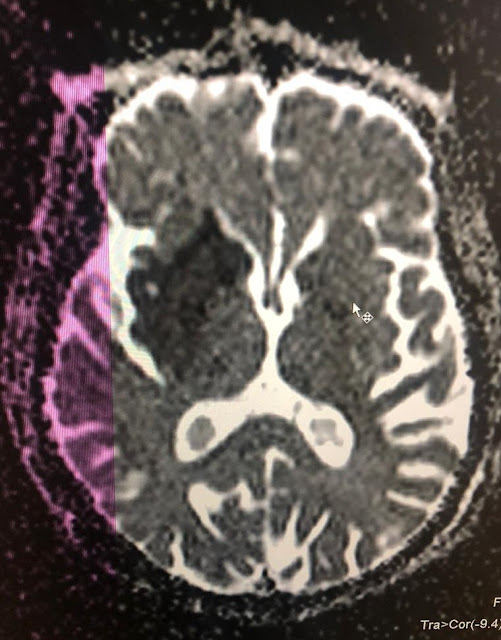

MRI BRAIN plain

Ischemic CVA with left sided Hemiplegia with UMN facial palsy 2° to infarct  In ? MCA territory